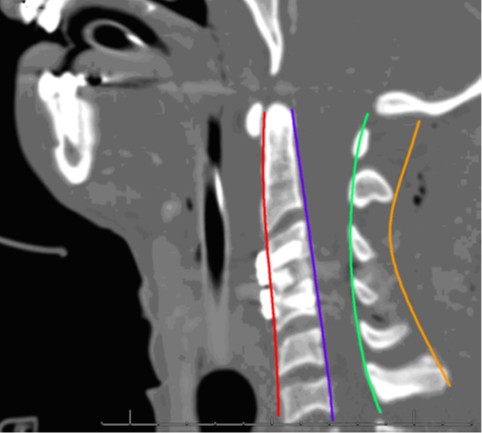

CTTS được xác định dựa trên lâm sàng và hình ảnh học (hình 2). Điều trị CTTS phụ thuộc vào việc chẩn đoán sớm, xác định thời gian bị tổn thương thần kinh để tiên lượng đáp ứng điều trị, và thực hiện mổ giải ép và cố định cột sống. Phân loại CTTS giúp đánh giá sự phục hồi thần kinh và tiên lượng kết quả điều trị. Phân độ ASIA do hội chấn thương cột sống Hoa Kỳ (ASIA) đề xuất là phân độ được sử dụng phổ biến nhất. Phân độ ASIA dựa trên đánh giá sức cơ, cảm giác, phản xạ, và chức năng ruột/bàng quang, được chia làm 5 độ (bảng 1).

Hình 2. Xquang giải phẫu đốt sống: Dựa vào các đường cong sinh lý là phương pháp nhanh chóng để đánh giá tình trạng dịch chuyển và mất vững tiềm ẩn.